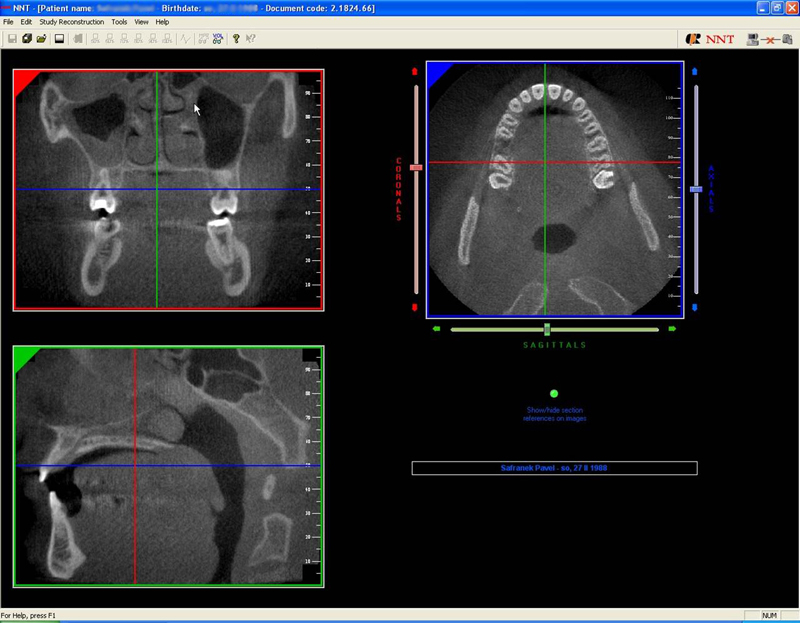

NewTom Implant Planing

Jedná se o plánovací program, který využívá dat získaných při vyšetření pomocí přístroje New Tom. Tento program umožňuje tříprostorovou počítačovou simulaci při plánování pozic implantátů.

Součástí programu je i databáze, ve které mohou být uloženy všechny typy implantátů od všech výrobců, včetně jejich délek, průměrů i tvarů.

Lékař si vytvoří všechny typy zobrazení potřebných pro naplánování – tedy 2D snímky (panoramatický), příčné řezy i 3D model.

Vidí zde i důležité anatomické útvary – čelistní dutinu, průběh nervu atd. Po proměření množství kosti – šířky i výšky vybere z databáze vhodný typ implantátu a umístí ho do požadované lokality.

Ihned vidí jeho pozici ve všech 3 rovinách a na všech snímcích i 3D modelu. Může upravovat podle potřeby jeho pozici, sklon atd.

Všechny vybrané a správně umístěné simulované implantáty se ukládají do „počítačové karty“ pacienta s jejich pozicí, délkou, průměrem, typem i sklonem.

Lékař i pacient tedy ještě před vlastní operací vidí, jak by mělo ošetření probíhat a vypadat.